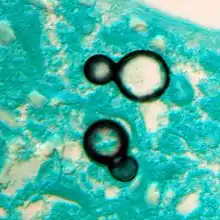

Once suspected, the diagnosis of blastomycosis can usually be confirmed by demonstration of the characteristic broad based budding organisms in sputum or tissues by KOH prep, cytology, or histology.[27] Tissue biopsy of skin or other organs may be required in order to diagnose extra-pulmonary disease. Blastomycosis is histologically associated with granulomatous nodules.